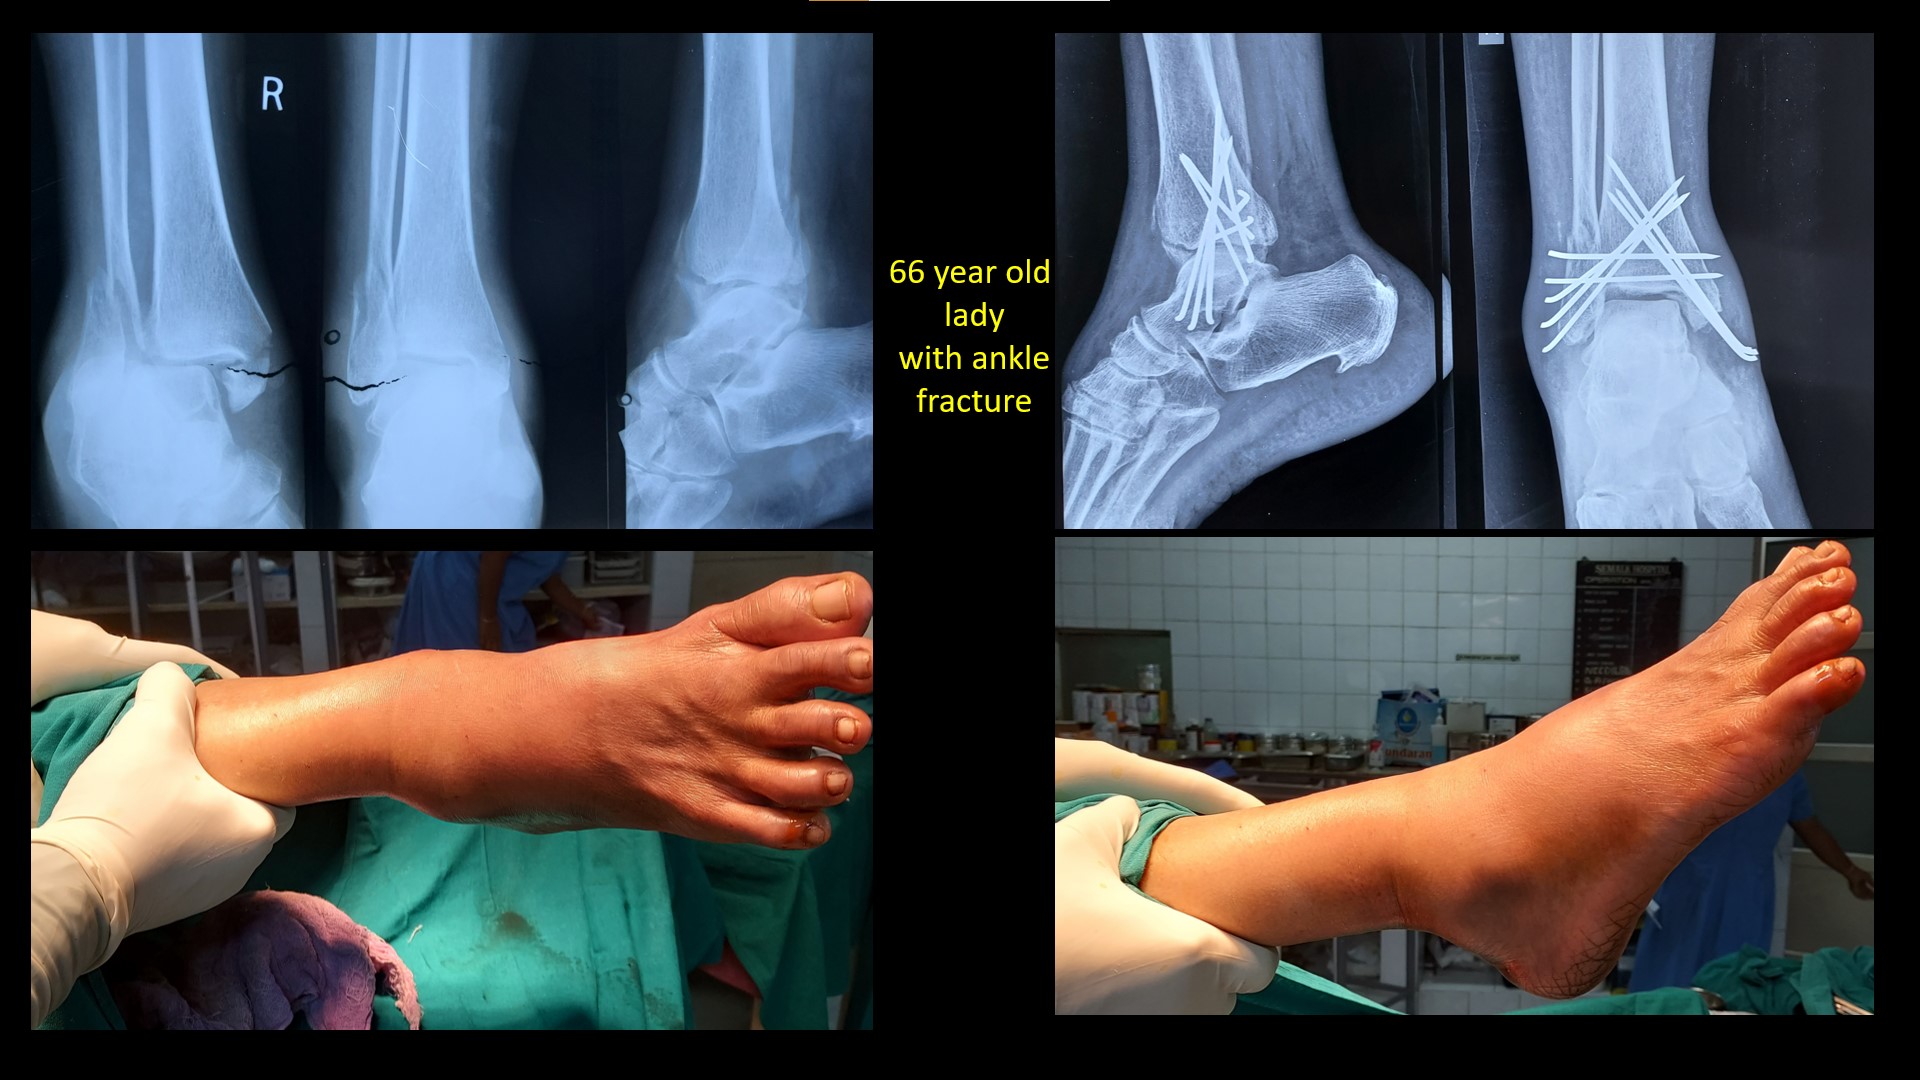

ANKLE